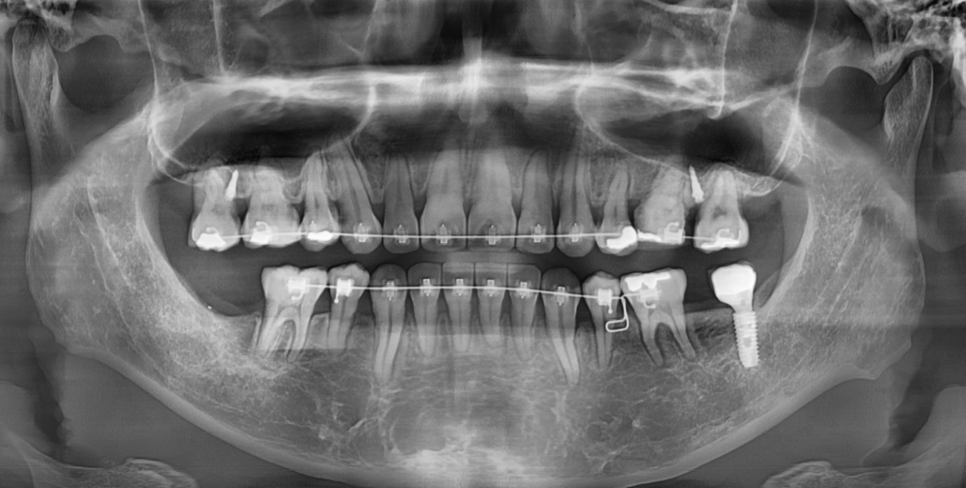

치아에 장치를 붙이는 경우에

철사를 넣어 교정을 진행합니다.

교정 치료에서 철사(와이어)는

브라켓에 연결되어 치아에 지속적인 힘을 가해 움직이게 하는 핵심 부품이에요.

교정 초기와 후반부에 사용하는 와이어 역할이 다릅니다.

교정 중간~후기에는 굵고 단단한 철사를 사용합니다.

강한 힘을 지속적으로 주어

치아의 세밀한 정렬을 도와주죠